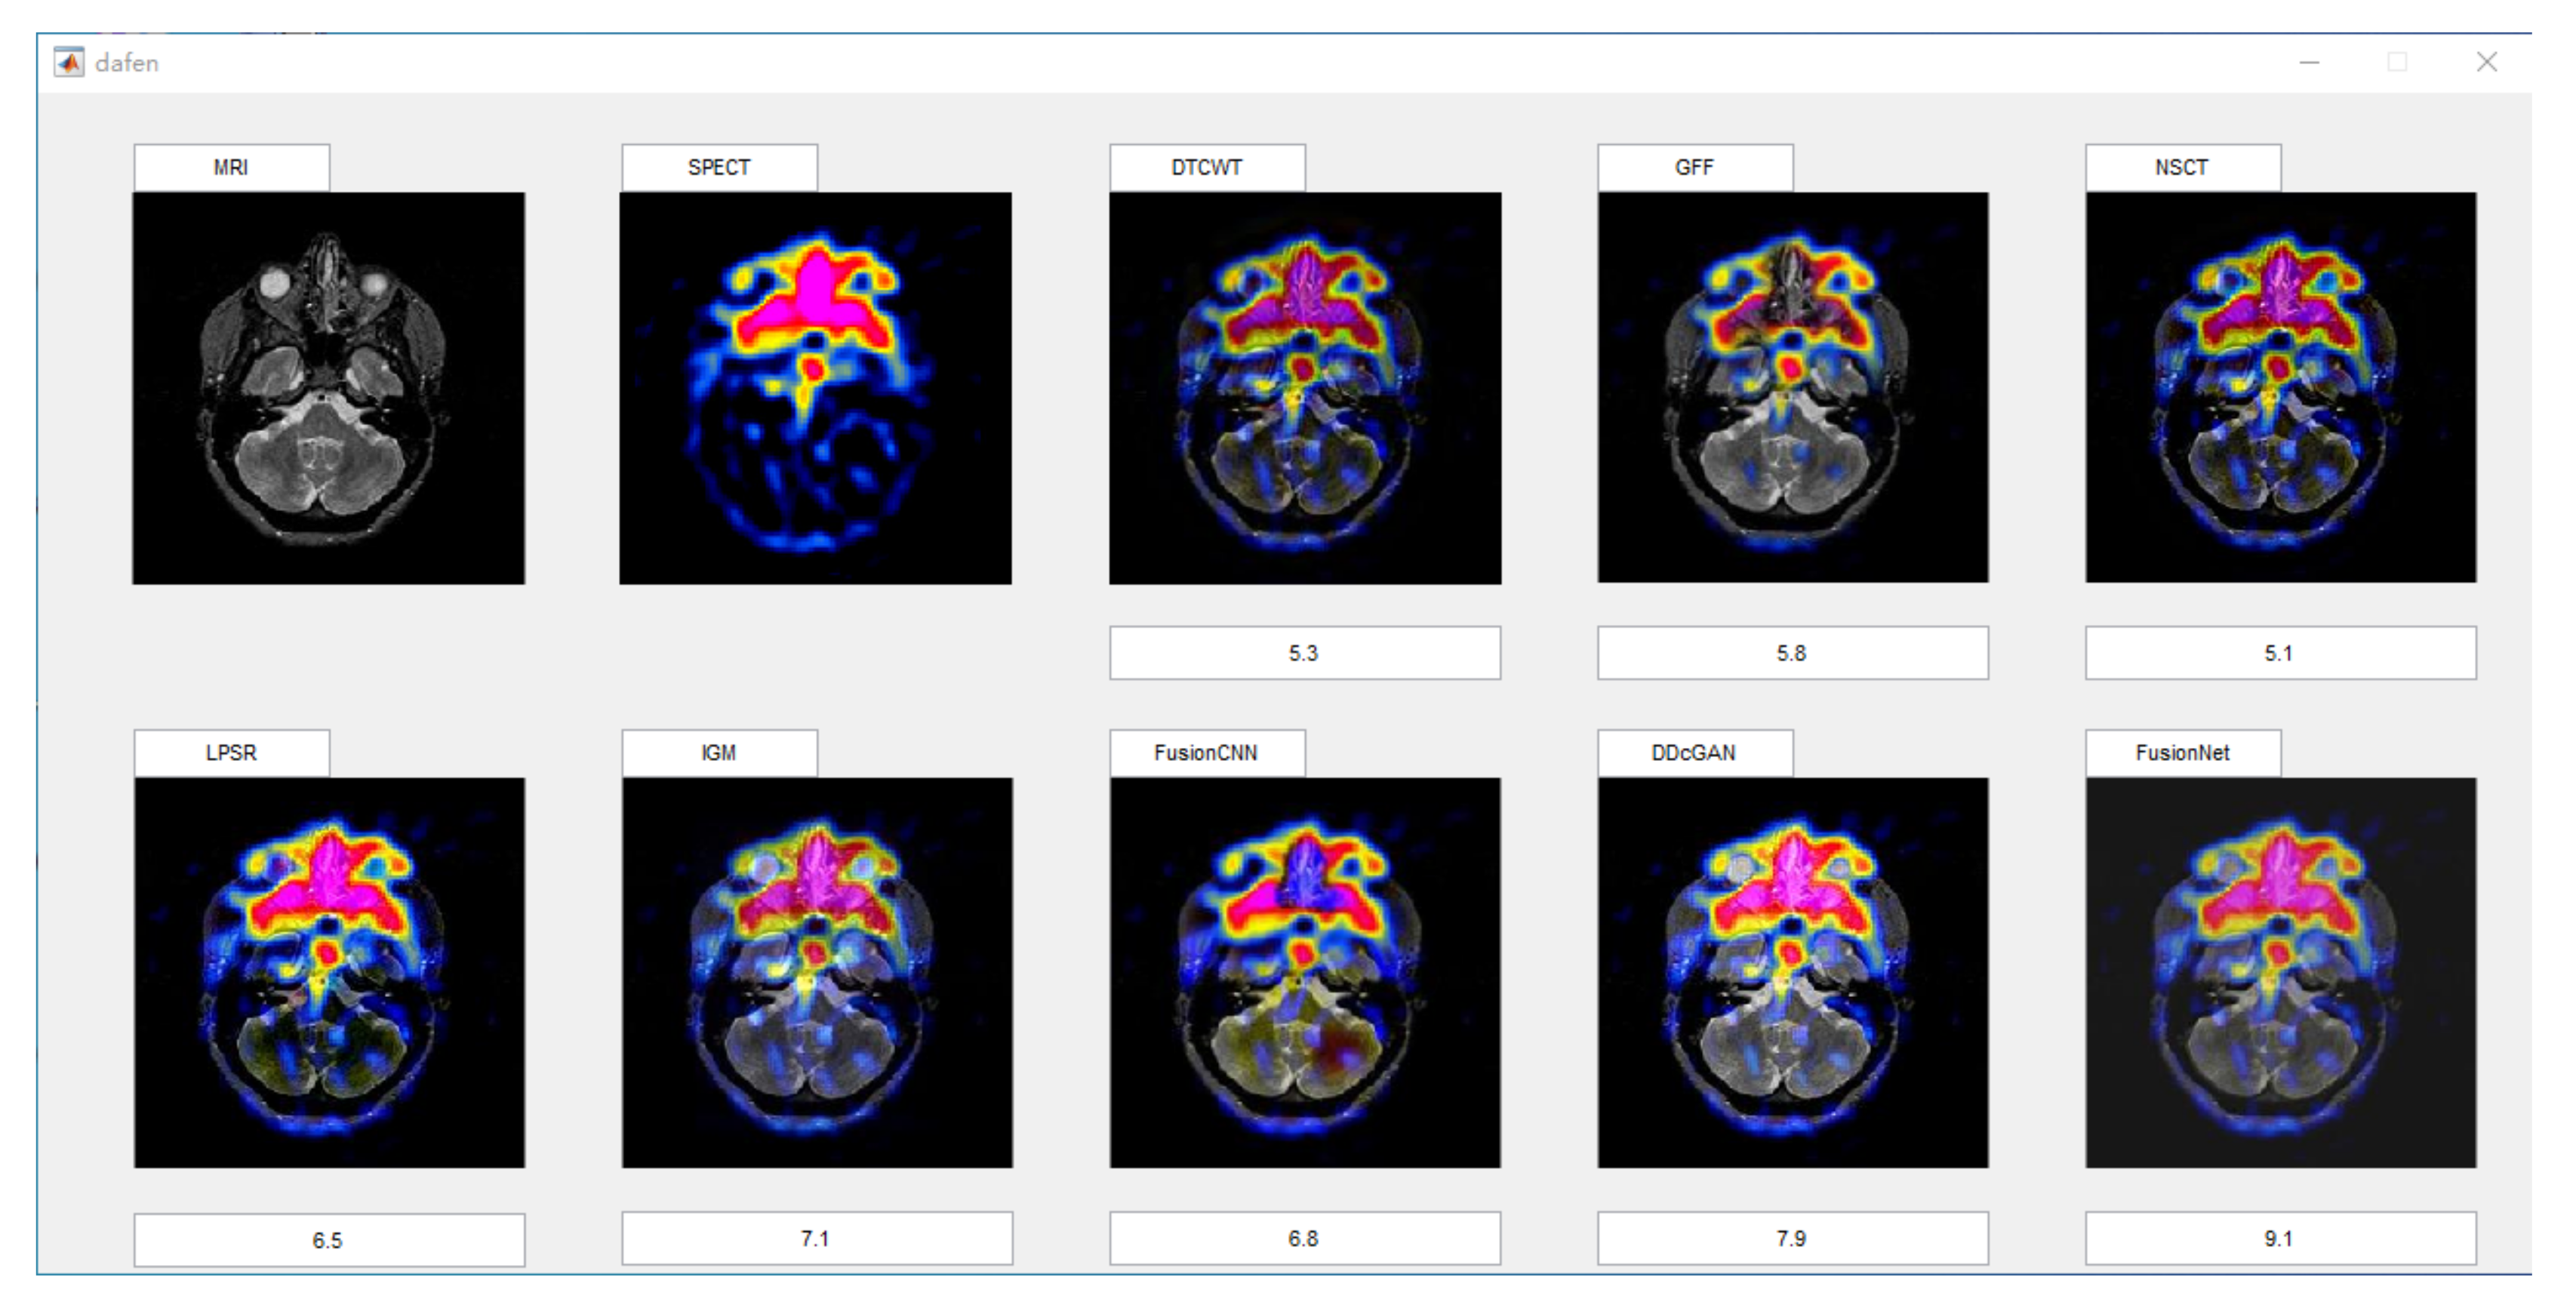

In this section, all FDG images are derived from the normal human brain, but the angle is chosen differently in Figure 24. In Figure 25, Figure 26, Figure 27 and Figure 28, we find that the color information obtained by the image fusion method based on NSCT, DTCWT, and LPSR is better preserved, but the structure information is lost more. The fusion image based on GFF, IGM, and FusionCNN method retains the complete structure information in the MRI image, but the color obtained from the FDG image is distorted. The image color information obtained by DDcGAN fusion method is too bright, resulting in unclear color area details and low contrast of color region. In contrast, the image obtained by our algorithm has moderate brightness of color information, complete structure information, and complete biological detail information.

Figure 24.

Four pairs of MRI-Fludeoxyglucose (FDG) source images: (a,c,e,g) are MRI images; (b,d,f,h) are FDG images.

Figure 25.

Fused medical images obtained by different algorithms (Figure 24a,b): (a) DTCWT, (b) GFF, (c) NSCT, (d) LPSR, (e) IGM, (f) FusionCNN, (g) DDcGAN, and (h) FusionNet.

Figure 26.

Fused medical images obtained by different algorithms (Figure 24c,d): (a) DTCWT, (b) GFF, (c) NSCT, (d) LPSR, (e) IGM, (f) FusionCNN, (g) DDcGAN, and (h) FusionNet.

Figure 27.

Fused medical images obtained by different algorithms (Figure 24e,f): (a) DTCWT, (b) GFF, (c) NSCT, (d) LPSR, (e) IGM, (f) FusionCNN, (g) DDcGAN, and (h) FusionNet.

Figure 28.

Fused medical images obtained by different algorithms (Figure 24g,h): (a) DTCWT, (b) GFF, (c) NSCT, (d) LPSR, (e) IGM, (f) FusionCNN, (g) DDcGAN, and (h) FusionNet.